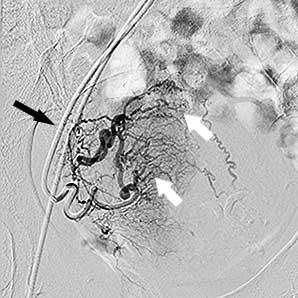

UFE

Ендоваскулярний хірург робить прокол шкіри голкою в паховій складці або руці та, потрапивши в артерію, вводить туди тонку (1,5–2 мм), спеціально зігнуту трубку — катетер. Оскільки процедура малоболісна, використовується лише місцева анестезія, яку доповнюють препаратами для легкого медикаментозного сну. Хірург під рентгенівським контролем проводить катетер артеріями до матки — спеціальна апаратура дозволяє стежити за переміщенням катетера всередині тіла. Катетер по черзі підводиться до правої та лівої маткової артерії. Далі виконується артеріограма — введення в маткову артерію спеціальної контрастної речовини, видимої під рентгеном, що дозволяє "побачити" фіброміому і підтвердити правильне розташування катетера.

міома матки до емболізації    міома матки до емболізації

Права маткова артерія:

чорна стрілка - катетер, білі стрілки -

розширені артерії вузла

Ліва маткова артерія: